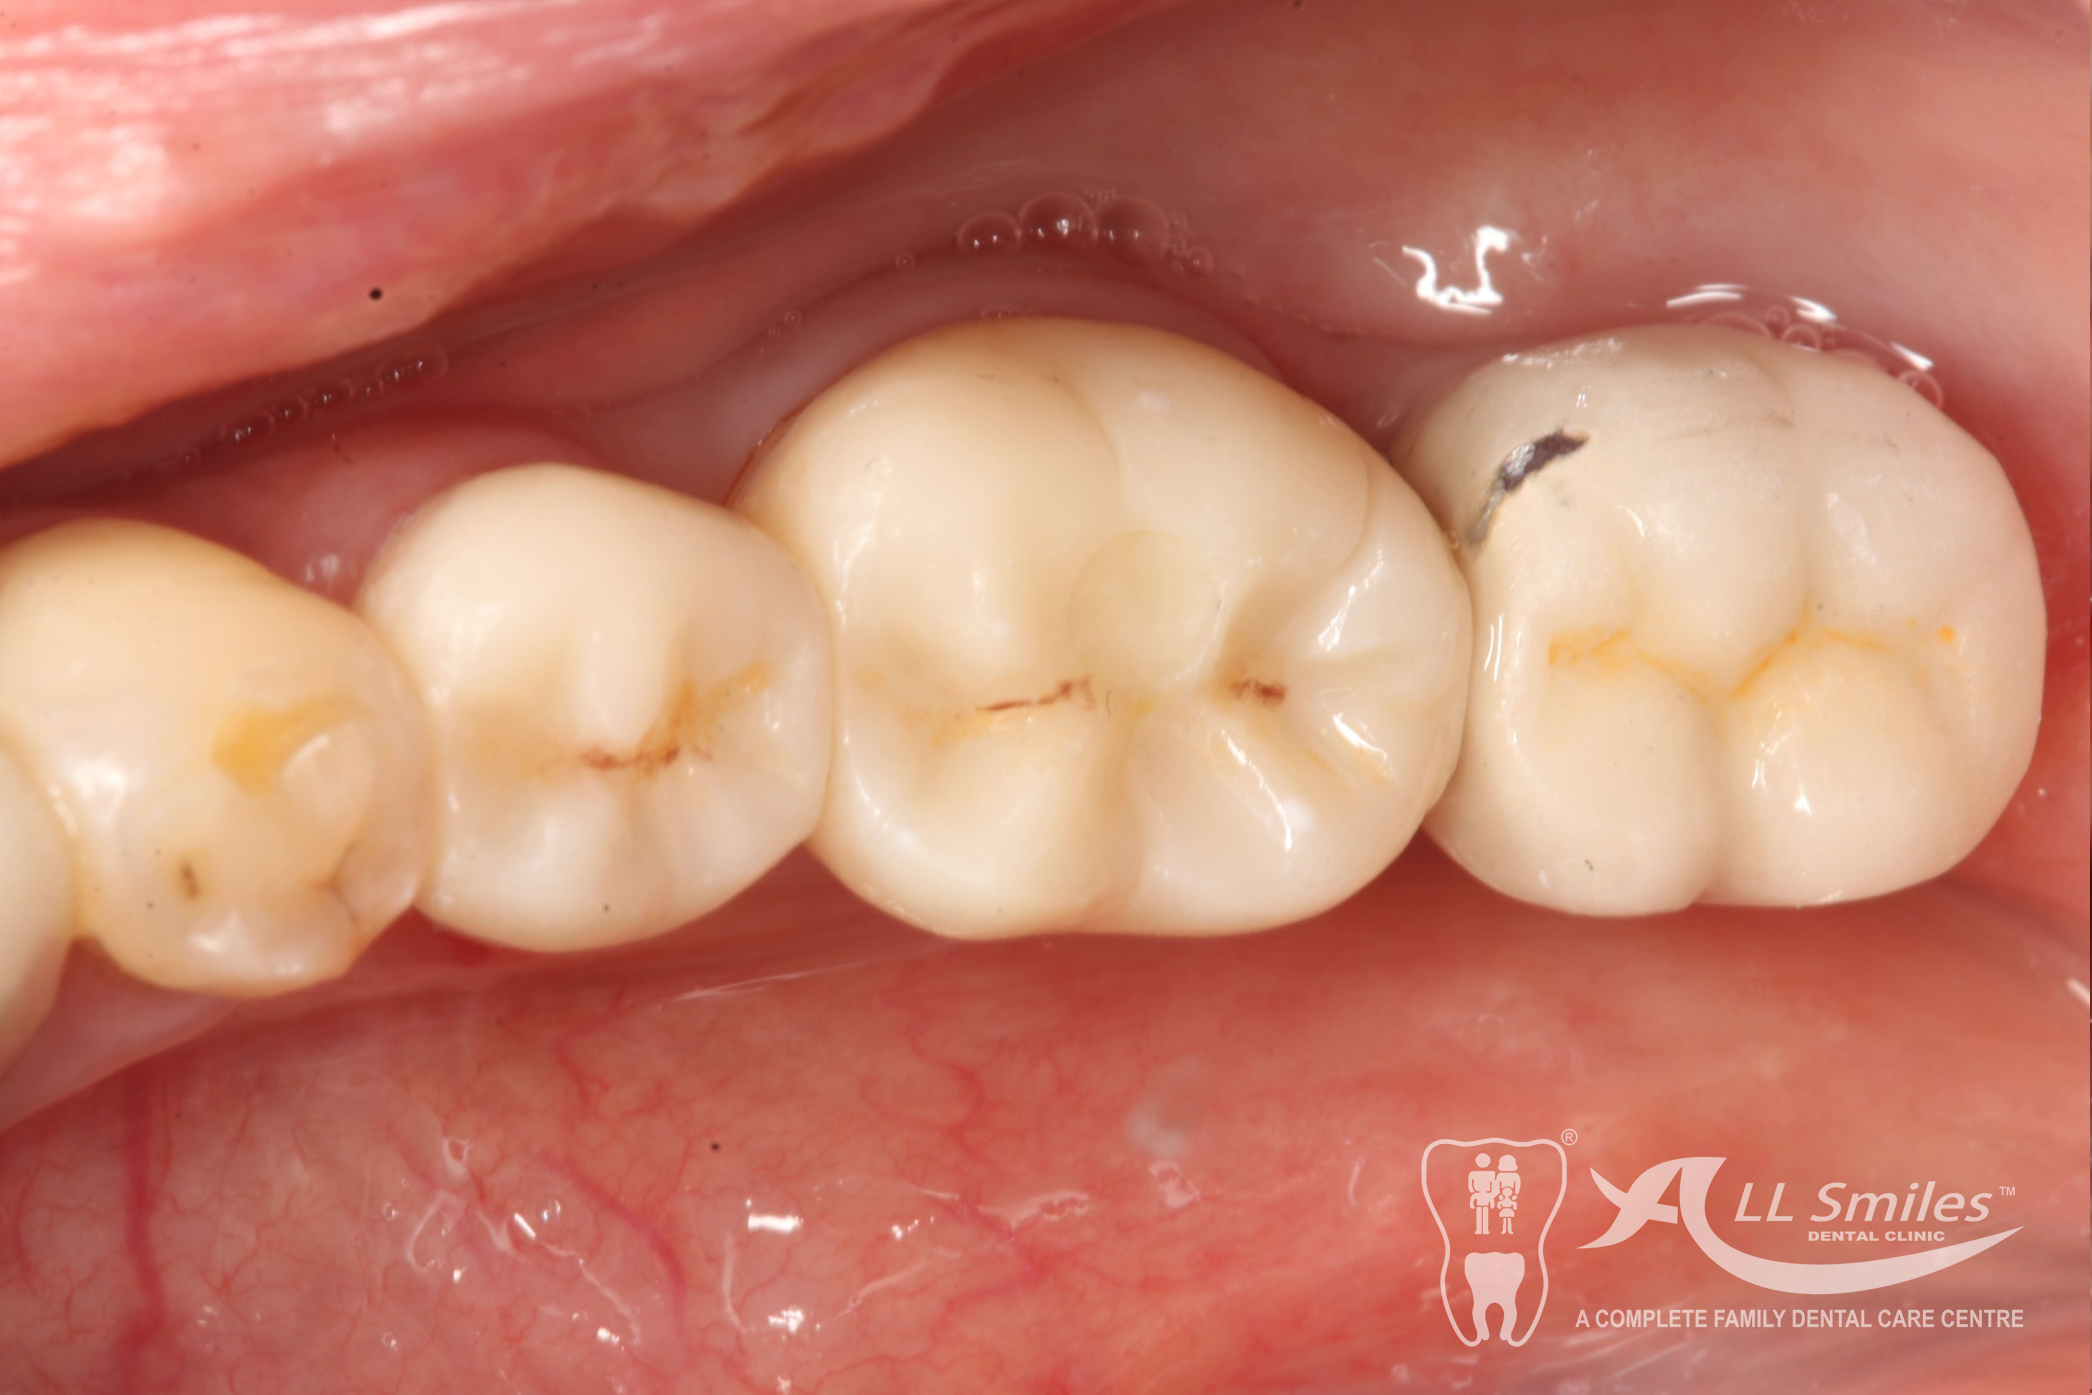

Dental Implants Gallery